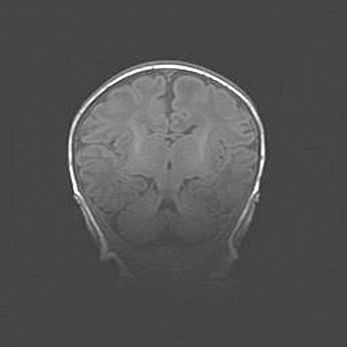

Наружная гидроцефалия с возможной атрофией височных областей.

Возраст: 28 дней

Вес: 3670 г

Пол: мужской

Окружность головы: 38 см

Срок гестации: 40 недель

Гидроцефалия головного мозга у новорожденных – это заболевание, которое характеризуется скоплением избыточного количества спинномозговой жидкости в желудочковой системе головного мозга в результате затруднения её перемещения от места выработки к месту поглощения в кровеносную систему или вследствие нарушения абсорбции. При открытой наружной форме гидроцефалии у новорожденных расширяются и переполняются субарахноидные пространства.

При нормотензивных  формах,  которые,  как  правило,  являются  следствием  перенесенных ишемических  повреждений  паренхимы  мозга,  возможно  сочетание микроцефалии  с нормотензивной гидроцефалией. В основе данных изменений лежит атрофия больших полушарий с преимущественной  локализацией  в  лобно-височных  областях.